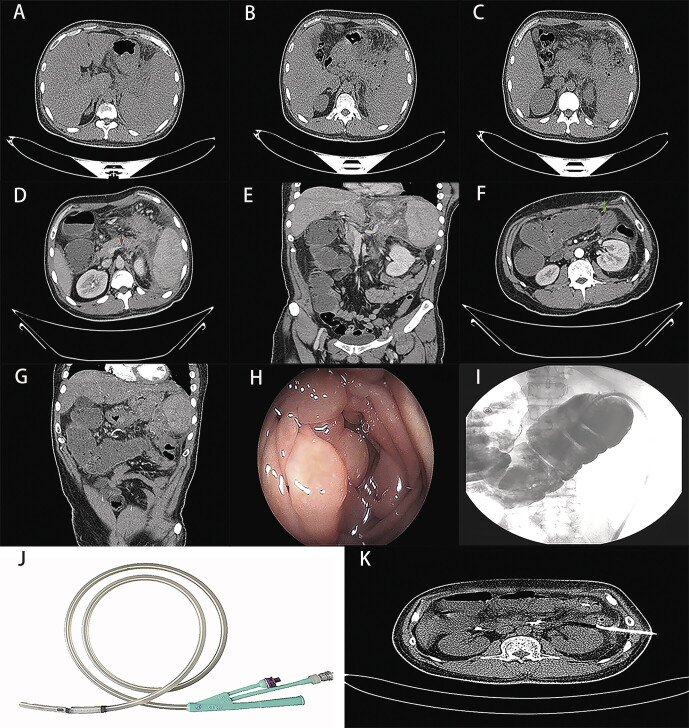

急性坏死性胰腺炎(ANP)通常伴有急性坏死集结(ANC)或贴壁坏死(WON)。由于胰腺、脾脏和横结肠之间存在密切的解剖学联系,坏死性胰腺炎常常合并脾脏或结肠受累。胰腺炎通常会引起胃肠道功能障碍,导致麻痹性肠梗阻。然而,胰腺炎合并机械性结肠梗阻的情况极为罕见。它很容易被误诊为恶性肠梗阻,如果伴有窦性门静脉高压症(SPH),诊断肠梗阻的病因就变得更加重要。手术切除是之前发生结肠并发症的主要方法。在本病例报告中,一名 37 岁的患者入院时被诊断为急性坏死性胰腺炎伴窦状门静脉高压症。入院后第 6 天,患者突发结肠梗阻。查明病因后,患者接受了经肛门减压管和微创坏死切除术,避免了结肠切除。急性坏死性胰腺炎合并结肠机械性梗阻时,必须明确病因,将治疗重点放在清除胰周坏死组织上,非手术治疗结肠梗阻是可行的,个体化治疗原则应贯穿整个疾病。

Acute necrotizing pancreatitis (ANP) is often associated with acute necrotic collection (ANC) or walled-off necrosis (WON). Due to the close anatomical connection between the pancreas, the spleen, and the transverse colon, necrotizing pancreatitis is often combined with spleen or colon involvement. Gastrointestinal dysfunction usually caused by pancreatitis leads to paralytic intestinal obstruction. However, pancreatitis combined with mechanical colonic obstruction is extremely rare. It can easily be misdiagnosed as malignant intestinal obstruction, and diagnosing the cause of intestinal obstruction becomes more critical when accompanied by Sinistral portal hypertension (SPH). Surgical resection is the primary method for the previous occurrence of colonic complications. In this case report, upon admission, a 37-year-old patient was diagnosed with acute necrotizing pancreatitis with sinistral portal hypertension. On the 6th day after admission, the patient developed a sudden colonic obstruction. After identifying the cause, the patient underwent a transanal decompression tube and minimally invasive necrosectomy, avoiding colon resection. In acute necrotizing pancreatitis combined with colonic mechanical obstruction, it is essential to clarify the etiology, and focus treatment on clearing the peripancreatic necrotic tissue, non-surgical treatment to deal with colonic obstruction is feasible, and the principle of individualized treatment should be used throughout the disease.